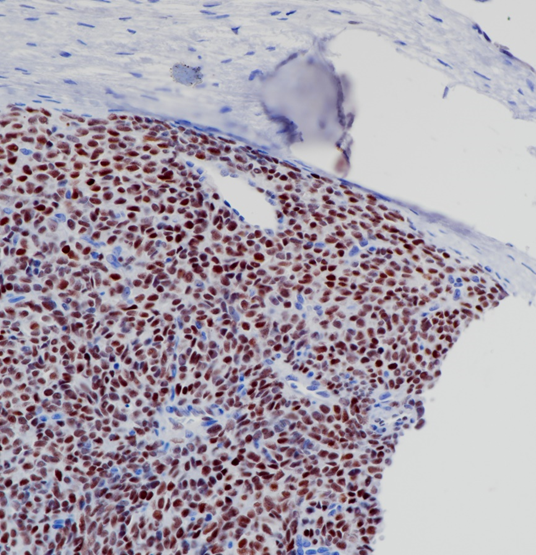

滑膜肉瘤TLE1(BP6223)染色

TLE 1与许多转录因子结合。它可以抑制NF-kappa-B调控的基因表达,也可以抑制FOXA 2、Wnt信号中CTNNB 1和TCF家族成员介导的转录激活。它增强FOXG1/BF-1-和HES 1介导的转录抑制。TLE 1在正常和癌症组织中广泛表达。TLE1通常用于滑膜肉瘤的诊断。

目录号

BX50246

克隆号

BP6223

阳性对照

滑膜肉瘤

亚细胞定位

细胞核

组织类型

FFPE

修复方式

HIER

稀释比

1:100-1:200

规格

100μl/vial, 1ml/vial

用途

RUO